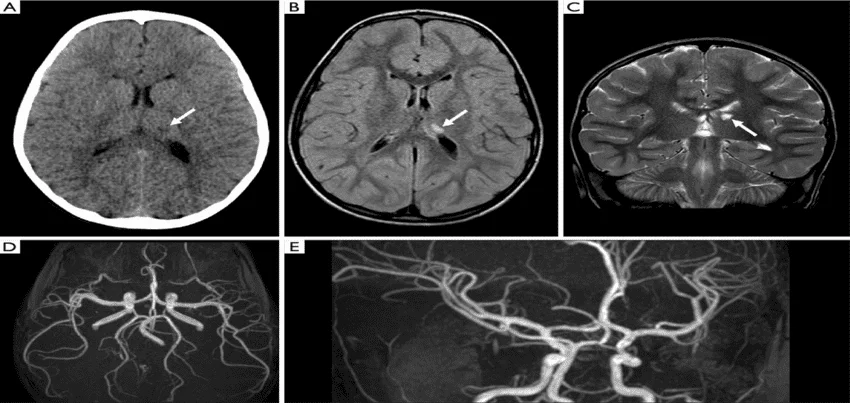

A Brain MRI, also known as an MRI Brain Scan, utilizes Magnetic Resonance Imaging of the Brain to provide detailed images of brain structures. For a comprehensive evaluation, a Brain Angiography can be performed alongside the MRI. This combined MRI Angiography Brain procedure, often referred to as an MRI Brain with Angiogram, visualizes the blood vessels within the brain, aiding in the diagnosis of vascular conditions. The MRI Brain Angiography Procedure involves the injection of a contrast agent to enhance the visibility of blood vessels, making it a crucial step in the Brain Angiography Procedure. The cost of an MRI Angiography Brain varies depending on the healthcare facility, but it is generally considered a valuable investment for accurate diagnosis. The Brain Angiography Interpretation provides insights into abnormalities such as aneurysms or blockages. An MRI Brain Test, when combined with Angiography, becomes an Angiography Brain Test, offering a dual advantage of structural and vascular assessment. The Angiography MRI Brain technique is pivotal in identifying and treating brain disorders. For those wondering, “What Is A Brain Angiography MRI?” it is a specialized imaging technique combining Brain MRI with Angio, essential for a thorough evaluation. Understanding the Brain Angiography Cost and MRI Brain with Angio benefits helps in making informed healthcare decisions.

Magnetic Resonance Imaging (MRI) Brain + Angiography is a medical imaging test that uses a strong magnetic field and radio waves to create detailed images of the brain and its blood vessels. This non-invasive procedure allows doctors to detect abnormalities or injuries in the brain and the blood vessels that supply it.

The interpretation of MRI Brain + Angiography images requires specialized training and experience. The radiologist will examine the images and prepare a report for the patient’s doctor. The report may indicate the presence of any abnormalities or injuries in the brain or blood vessels, the size and location of any tumors, and the extent of any blockages or abnormalities in the blood vessels.